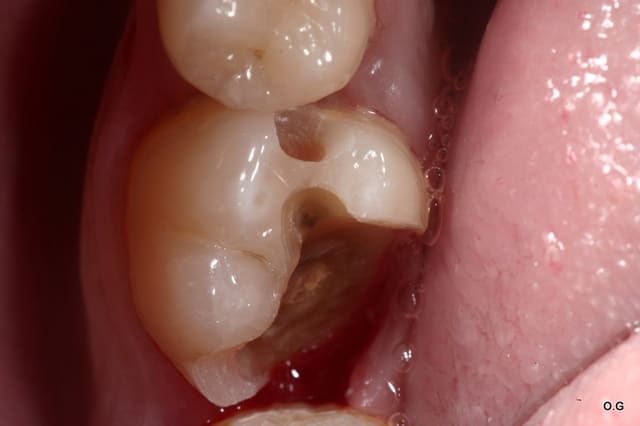

Onlay emax à 5 ans... contrôle la semaine dernière...

Dans cette situation, que donnerait un composite ?

tiens c'est bizarre , sur la dernière photo de cingulum (magnifique travail d'ailleurs) , la dent est toujours sur l'arcade alors que le joint semble être juxta voir sous gingival. Il m'a semblé avoir lu plus haut qu'un joint en compo ça se carie automatiquement au bout de cinq ans....

Allez cingulum , arrête de nous faire marcher, fais peter la radio avec la reprise de carie, l'endo, l'IC et la CCM!